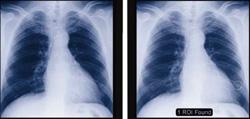

February 28, 2011 – Results from a study comparing two versions of computer-aided detection (CAD) technology have been published on the European Society of Radiology’s website. The study, which compared Riverain Medical’s OnGuard 1.0 and OnGuard 5.1, found that radiologists using OnGuard 5.1 were able to detect smaller lung nodules, including those that were primary lung cancer. "By using OnGuard 5.1 in tandem with a standard chest X-ray, our radiologists are now able to detect smaller lung nodules that would have previously gone unnoticed," said Matthew Freedman, M.D., principal investigator of the study and associate professor of oncology at the Lombardi Comprehensive Cancer Center at Georgetown University in Washington, D.C. "It's clear from our research that OnGuard CAD technology has improved significantly over the past 10 years. Improved sensitivity and a lower false positive rate allow radiologists to detect early-stage lung cancer sooner, giving them more confidence in diagnosing the patient." Fifteen radiologists participated in the reader study, which analyzed more than 250 chest X-rays (approximately a 2:1 cancer negative to positive ratio). Compared to its previous version, investigators found OnGuard 5.1 provided nearly 50 percent higher machine sensitivity for cancer detection, while significantly reducing the number of false positives per image. "Initial results of the National Lung Screening Trial demonstrate for the first time that the early detection of lung cancer can save lives," said Steve Worrell, chief technology officer of Riverain Medical. "We're excited to play a key role in the early detection of lung cancer. OnGuard's CAD markings give radiologists a second set of eyes, allowing radiologists to find cancerous nodules at their earliest and most treatable stage." For more information: www.riverainmedical.com